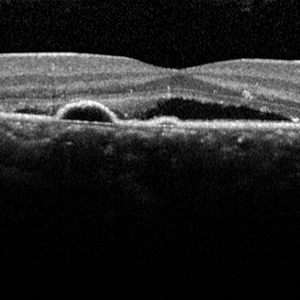

Central serous chorioretinopathy (CSCR)

CSCR is an acute condition where fluid collects underneath the retina and causes a limited retinal detachment. If this involves the macula, the most sensitive part of the retina, it results in blurring of vision. There is a strong association of this condition with steroid use. Although usually self-resolving, sometimes the fluid does not improve and there is a risk of permanent visual impairment. In this situation need treatment mainly by photodynamic therapy which is delivered using a special kind of laser.